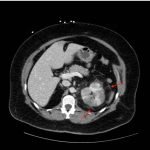

A CT abdomen and pelvis with IV contrast showed neither nephrolithiasis nor diverticulitis, and instead showed heterogeneous enhancement of the left kidney with mild edematous enlargement and striated left nephrogram. Significant perinephric stranding (red arrows) was also noted and was consistent with severe acute pyelonephritis.